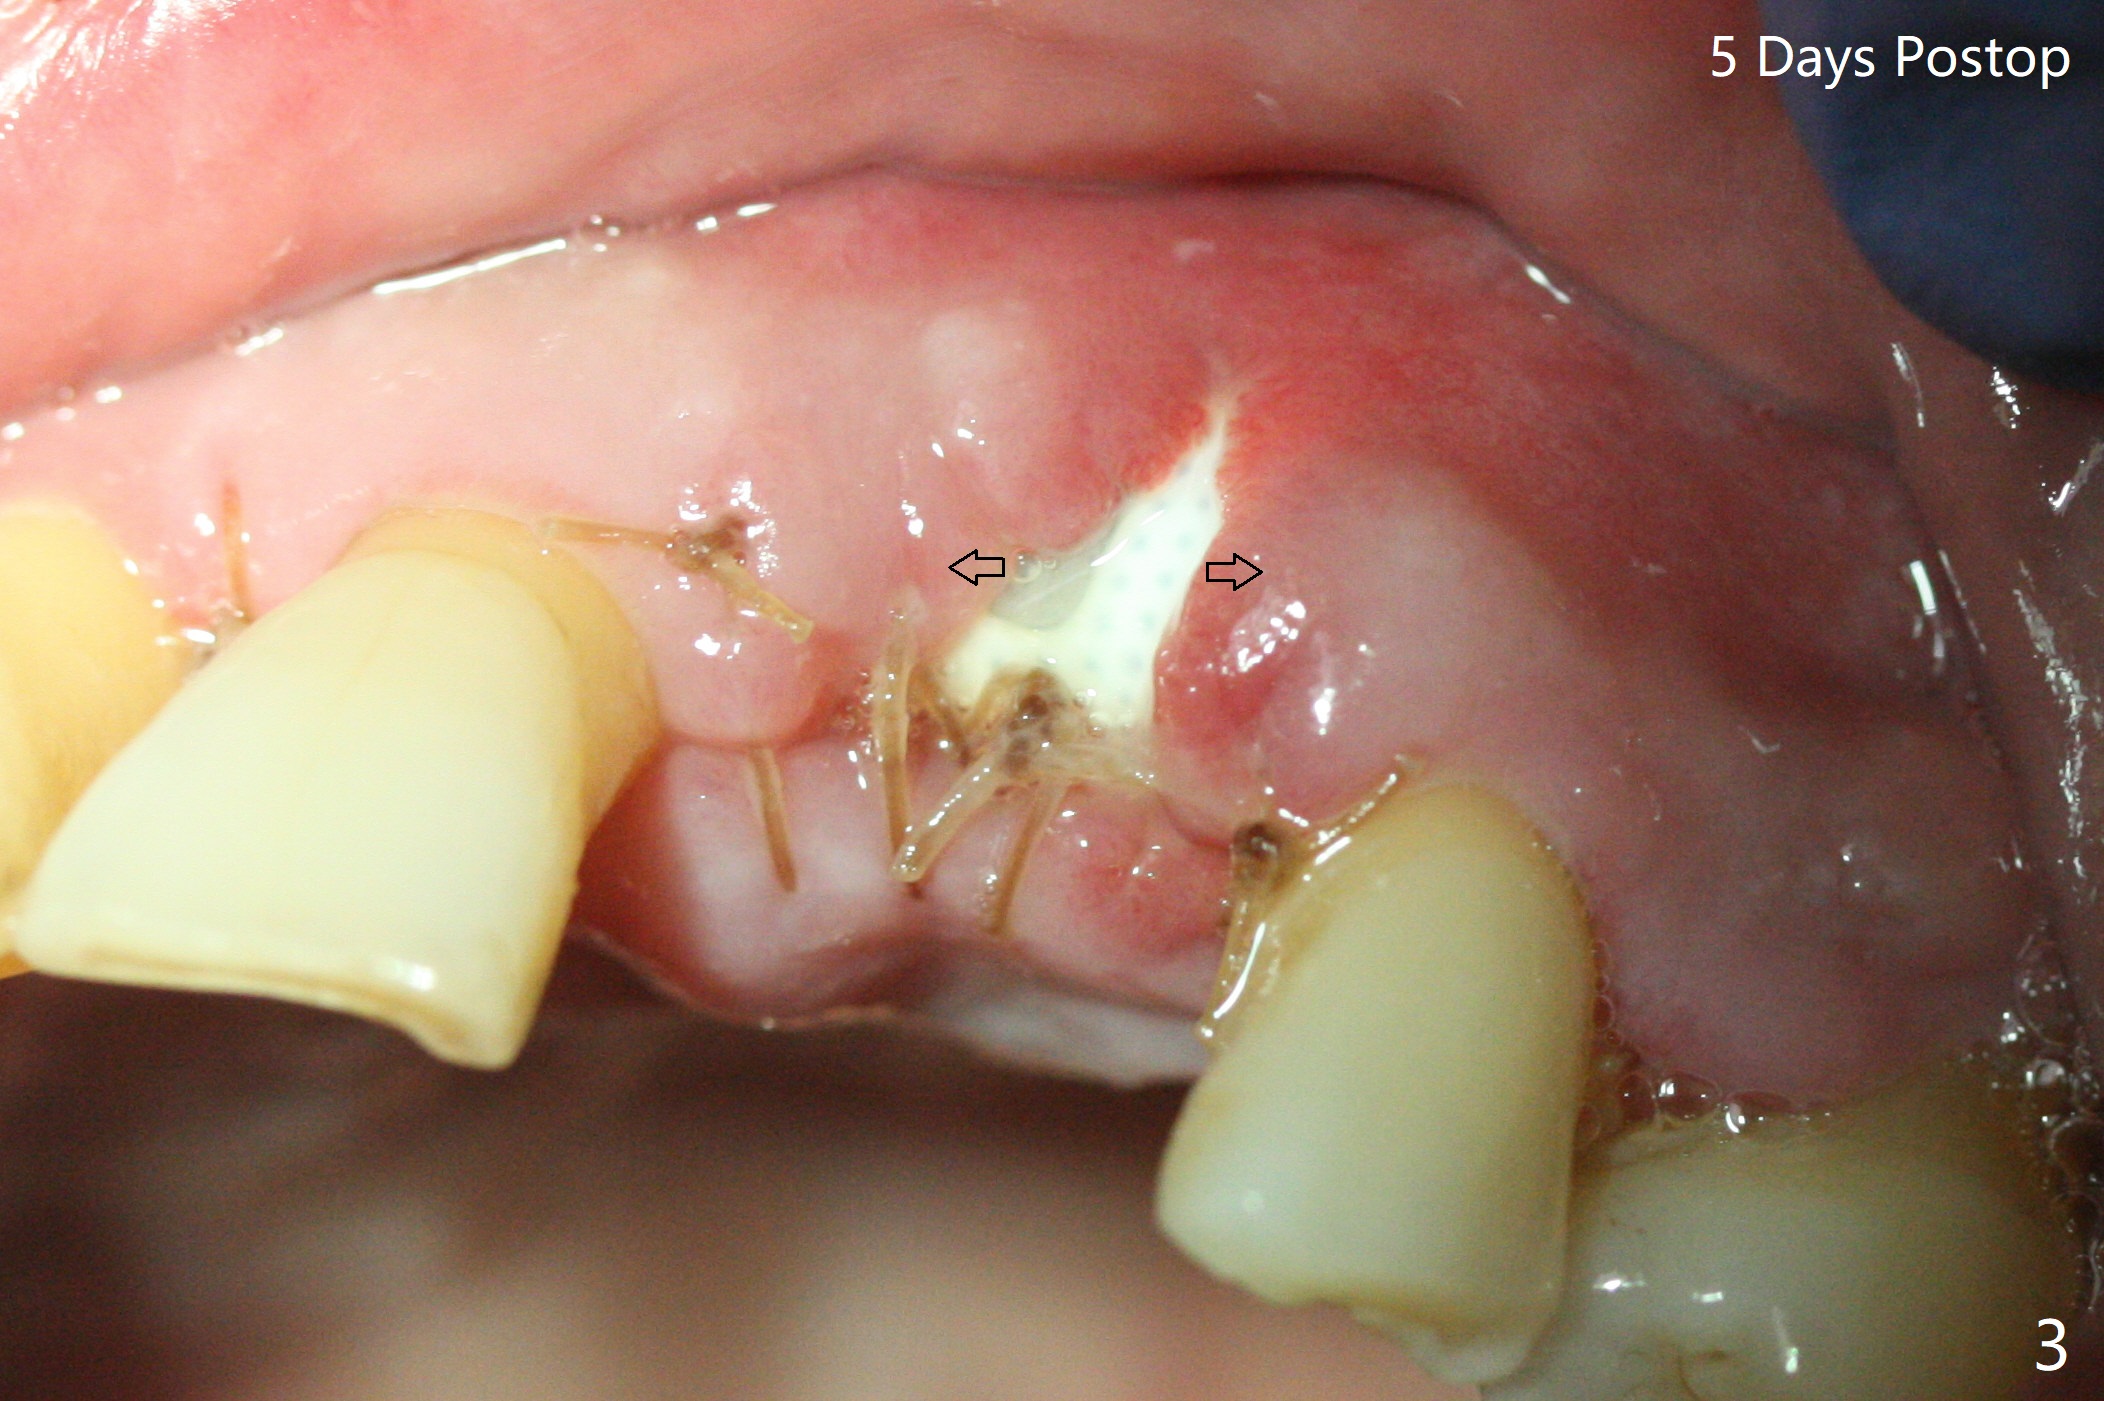

A 67-year-old man requests extraction of the loose tooth #9 (Fig.1). After extraction, the labial plate is found to be missing. With incision, allograft is kept in place with a 12x24 mm anterior narrow Cytoplast and 4-0 Chromic gut suture (Fig.2). Periodontal dressing dislodges in 2 days. The wound dehisces transversely 5 days postop (Fig.3 arrows), whereas the wound was open buccopalatal when the sutures were placed. Probably due to extensive dissection, the erythematous mucosa is large (Fig.4), although asymptomatic. When X-ray shows V-shaped bony defect (Fig.1 (PA), 5 (Pan), 6 (CT)), do not dissect the overlying thin buccal gingiva, which is most likely to dehisce. In fact immediate implant with guide appears to be more conservative, since there is no pressure against the buccal gingiva (Fig.7,8). To be more ideally, the implant could be placed more coronally, longer (13 mm instead of 11.5, Fig.9,10) and narrower (3.5 mm instead of 4.0 mm, Fig.11 (red circles: bone graft)).